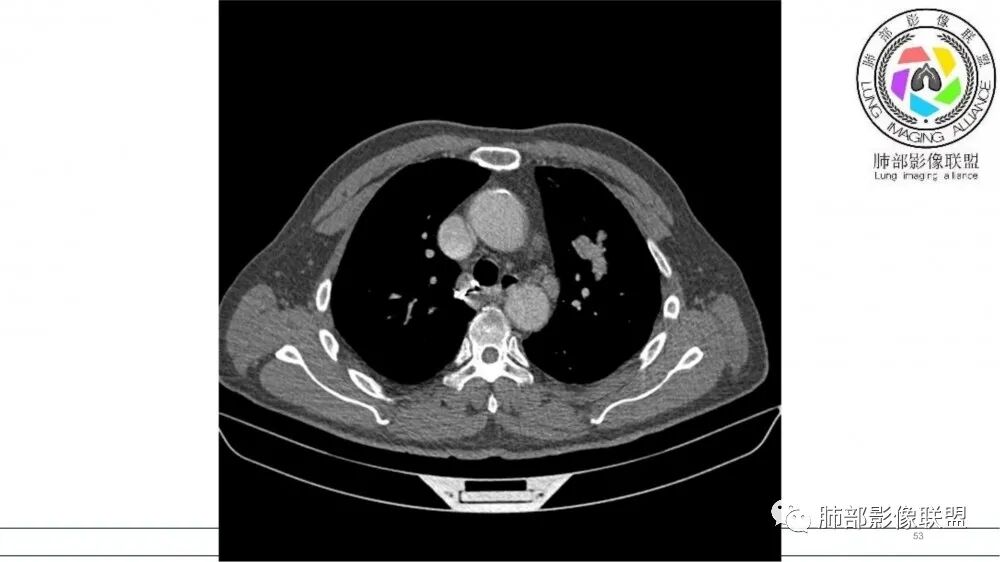

左肺上叶前段支气管内铸形生长软组织影,增强后均匀强化,远侧见斑片状磨玻璃影。考虑恶性病变,粘表?粘液腺?

老年男性,左肺上叶前段支气管内铸形阴影,增强后病灶不均匀强化,内部有坏死?远端可见斑片状阴影(阻塞性肺炎)。考虑恶性病变,老年人,鳞?类癌?粘表不能排除。

男,70岁,吸烟史,咳嗽,胸闷憋气一个月,左肺上叶不规则形软组织密度影,病灶沿支气管走形,周围见粟粒及棉絮样稍高密度影,增强扫描病灶内见少许坏死,考虑鳞癌可能,鉴别结核。

老年男性,肺气肿,吸烟史,左肺上支气管腔内铸型高密度影,呈指套状,远端多发树芽,增强不均匀强化,考虑鳞癌,鉴别小细胞癌

B3指套征,常规不是鳞癌就是ABPA,有强化丶血管造影征,倾向于鳞癌

老年男性,长期吸烟史。左上肺前段沿支气管走形的指套样病变,增强可见病灶强化(排除结核、ABPA(也无气喘症状)),远端多发点状高密度影。考虑恶性肿瘤,鳞癌可能性大。

指套征,扩张支气管内软组织强化,远侧肺野阻塞性炎,纵隔、左肺门肿大淋巴结;老年男性,吸烟,考虑鳞癌,鉴别小

老年男性,术前检查肺气肿背景,左肺上叶结节,沿支气管蠕虫样生长,左肺门及纵隔淋巴结肿大,增强扫描不均匀强化,血管包绕,结合吸烟史,考虑小细胞肺癌。

2021年8月6日晨读病例结果:小细胞肺癌

指套征:是影像征象,胸部平片表现为手指状密度增高影,以肺门为中心呈放射状分布,CT显示扩张支气管内低密度黏液栓形成或实性病变,呈管状、树枝状或卵圆形密度增高影;支气管扩张伴近端梗阻时,扩张支气管内部黏液分泌物不能排出而形成。可以伴随远端空气潴留征、阻塞性炎症。

研究报道,中心型 SCLC 经 CT 扫描后通常支气管表现为鼠尾样狭窄,肺门或纵隔肿块明显,由于肿块沿管壁生长表现为顺延支气管形态的不规则形状。病灶相对特征性影像学表现比如鸭蹼状、腊肠状、葫芦状及葡萄状改变,可以出现血管包埋,很少有空洞、空泡,较少引发肺不张,阻塞性炎症成都较轻。与一般肺癌比较,恶性程度高,侵袭力强、病灶很小就容易远处转移!Herzberg 等[19]研究指出,20%以上 SCLC 倍增时间短,预后不良。